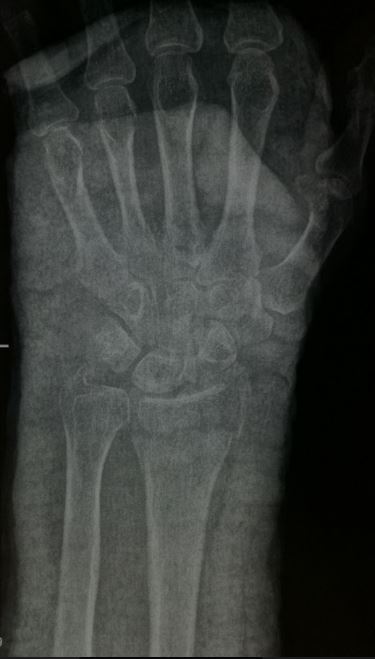

Jabka labada lafood ee u dhaxeeya xusulka iyo gacanta (Forearm fractures) badanaa waxaa keena jug toos ah oo ku dhacda lafta ama ilmaha oo gacanta oo u fidsan dhaca. Hal laf kaliya ayaa jabi karta ama labada lafood ayaa wada jabi kara; jabku wuxuu noqon karaa mid kala bax kala goyska xusulka ama kala goyska gacanta la socdo.

Raajo ayaa lagu xaqiijiyaa jabka; Xalka jabkana wuxuu ku xiran yahay da’da bukaanka iyo nuuca jabka, qaliinkana waxaa la sameeyaa hadii ay jiraan xaaladihii aan kusoo sheegnay qaybta xogta guud. Dhakhtarka ayaa mar kasto talada rasmiga dhiibaayo kadib markuu qiimeeyo xaalka bukaanka iyadoo bukaankuna go’aanka wax ku leeyahay.